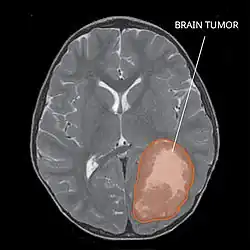

| Primitive neuroectodermal tumor of the central nervous system in a 5-year-old |

A central nervous system primitive neuroectodermal tumor, often abbreviated as PNET, supratentorial PNET, or CNS-PNET,[1] is one of the 3 types of embryonal central nervous system tumors (medulloblastoma, atypical teratoid rhabdoid tumor, and PNET).[2] It is considered an embryonal tumor because it arises from cells partially differentiated or still undifferentiated from birth.[1] Those cells are usually neuroepithelial cells,[1][2][3] stem cells destined to turn into glia or neurons.[4] It can occur anywhere within the spinal cord and cerebrum and can have multiple sites of origins, with a high probability of metastasis through cerebrospinal fluid (CSF).[1][2]

The rate of PNETs in not correlated with sex, but it shows a correlation with age.[1] Most cases occur in children around 5 years of age, having a very low frequency in adults.[1] Regarding genetic mutations, a specific type of gene alteration that directly leads to this tumor hasn't been defined yet.[1] However, a positive correlation between individuals with Li-Fraumeni syndrome with a mutation in the gene p53 and PNET has been reported.[2] A significant number of individuals with mutations on the rb tumor suppressor gene have also developed the tumor.[2] Such gene encodes for the protein Rb responsible for stopping the cell cycle at the G1 phase.[6] Another possible contributing factor are mutations in the CREB-binding protein, whose function includes activating transcription,[6] but this interaction still need to be studied further.[2] It has also been presumed that the tumor can arise from cranial irradiation.[2]

Most children that develop primitive neuroectodermal tumors are diagnosed early in life, usually at around 3–6.8 years of age.[2] Symptoms patients present at time of diagnosis include irritable mood, visual difficulties, lethargy, and ataxia.[2] The circumference of the patient's head might also become enlarged and they might be subject to seizures, especially if they have less than one year of life.[2]

Several analysis can be used to determine the presence of the disease. Physical examinations showing papilledema, visual field defects, cranial nerves palsy, dysphasia, and focal neurological deficits are evidences for possible tumor.[2] PNETs can also be spotted through computed tomography (CT) and magnetic resonance imaging (MRI).[2] In images produced by MRIs, an irregular augmentation among a solid mass will indicated the presence of tumor.[3] However, the results of MRIs are usually ambiguous in defining the presence for this specific tumor.[2] In CT scans, the presence of PNETs will be indicated by an elevated density and an increase in volume of the brain.[2] The CT scan can also show calcification,[3] which is present in 41-44% of PNET cases.[2] Since the tumor can be replicated in other parts of the nervous system through the cerebrospinal fluid (CSF), a CSF analysis can also be conducted.[2] A spinal MRI is a fourth type of analysis that is useful in investigating the level of tumor propagation to the spinal cord.[2]